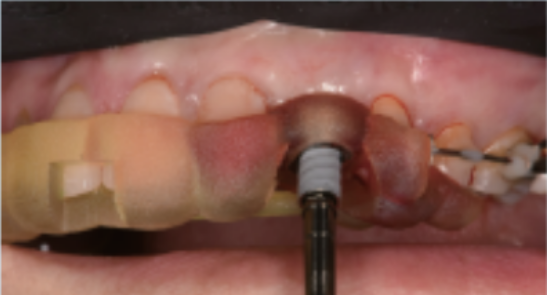

种植手术常规消毒、铺巾,局部浸润麻醉下,采用Luxator微创拔牙刀从患牙近远中腭侧切断牙周膜,牙钳拔出左上乳尖牙,注意保护唇侧骨板,搔刮窝洞,无菌生理盐水冲洗。

放置种植导板,待导板完全就位后,使用与导板配套的种植器械逐级预备种植窝洞,窝洞制备完成后植入种植体(Nobelactive3.5/11.5),植入扭矩(65N·cm),初期稳定性良好。

可以进行即刻修复,临时冠及基台就位,扭紧中央固位螺丝,扭矩(30N·cm)。最后封闭螺丝孔,检查咬合,应确保正中咬合、前伸咬合及侧方咬合均无接触。